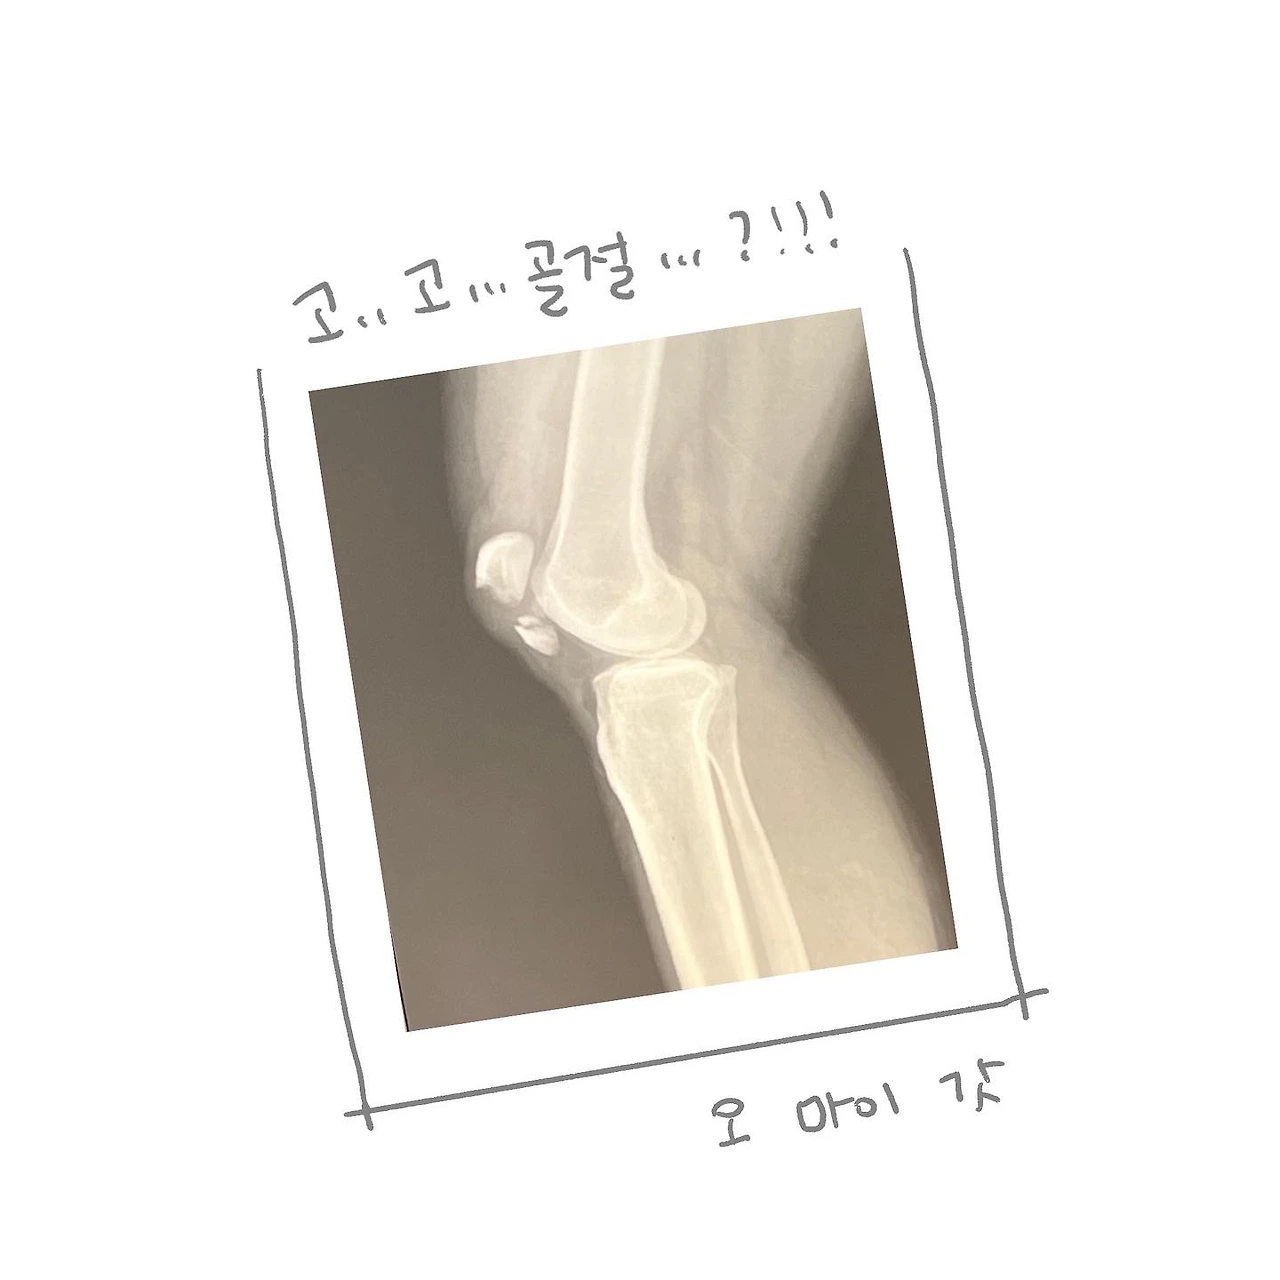

무릎 슬개골이 골절됐다.

다른 의사 말을 들었을 뿐인데 혼부터 났다. 입원실이 나지 않아서 응급실에서 24시간 대기를 하고 겨우 수술을 할 수 있었다. 두 동강 난 줄 알았던 슬개골은 열어보니 더 잘게 부서져 네 조각 나 있었고 2시간일 줄 알았던 수술은 그래서 더 오래 걸렸다고 했다.